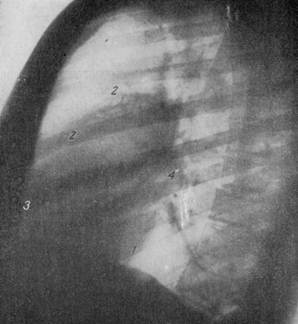

РЕНТГЕНОГРАММА НОРМАЛЬНОЙ ГРУДНОЙ КЛЕТКИ В ЛЕВОМ БОКОВОМ ПОЛОЖЕНИИ.

1 — дуга левого желудочка; 2 — дуга начальной части аорты; 3 — дуга правого желудочка; 4 — дуга левого предсердия.